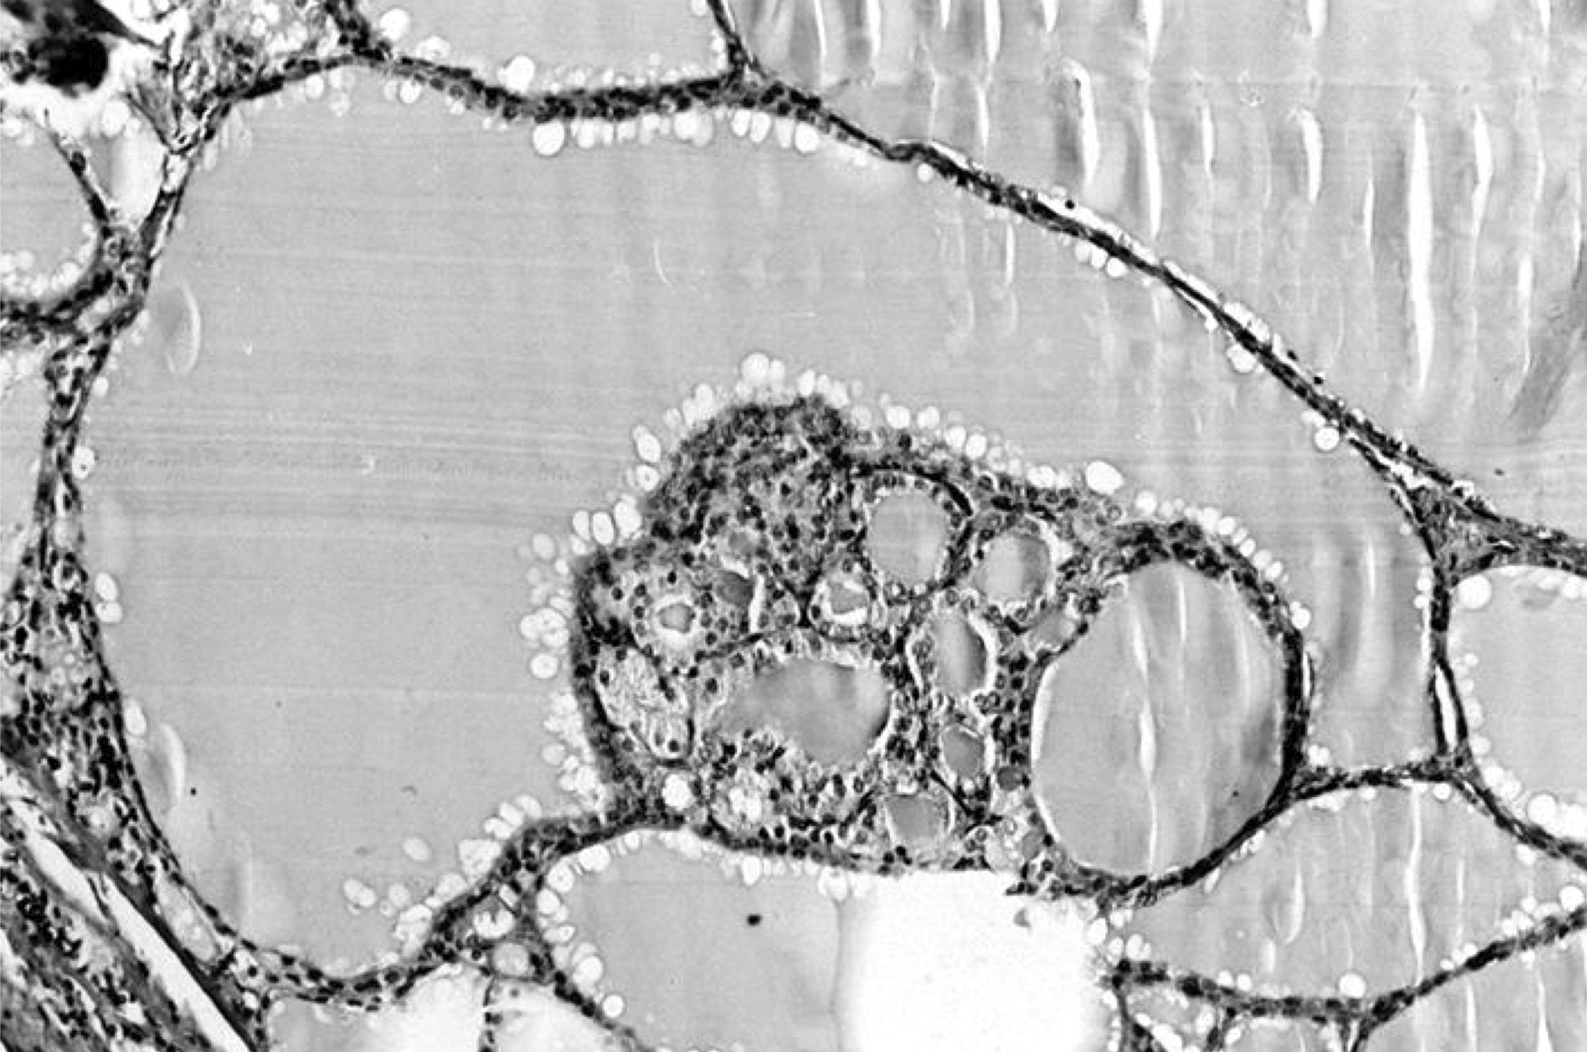

Microscopic (histologic) description

- Variable sized dilated follicles with flattened to hyperplastic epithelium

- Nodules with variable histological patterns: from colloid and microfollicular to hypercellular / microfollicular

- Some of the cystically dilated follicles may show papillary projections (Sanderson polsters) that may mimic papillary carcinoma; however, they lack the nuclear features of papillary carcinoma

Microscopic (histologic) images

Contributed by Swati Satturwar, M.D., Andrey Bychkov, M.D., Ph.D. and Rajeshwari K. Muthusamy, M.D.

AFIP images

C. Variably sized follicles with flattened hyperplastic epithelium, cysts, hemorrhage, granulomatous response, fibrosis, calcification or osseous metaplasia. Nodules may or may not be present in nodular goiter but generally lack a thick capsule. Prominent features are variably sized dilated follicles with flattened hyperplastic epithelium. Secondary changes include foci of fresh or old hemorrhage, rupture of follicles with granulomatous response, fibrosis, calcification and even osseous metaplasia. Some of the cystically dilated follicles may show papillary projections (Sanderson polsters). Cytologic atypia in the form of highly atypical nuclei occurs in patients exposed to radioactive substances.